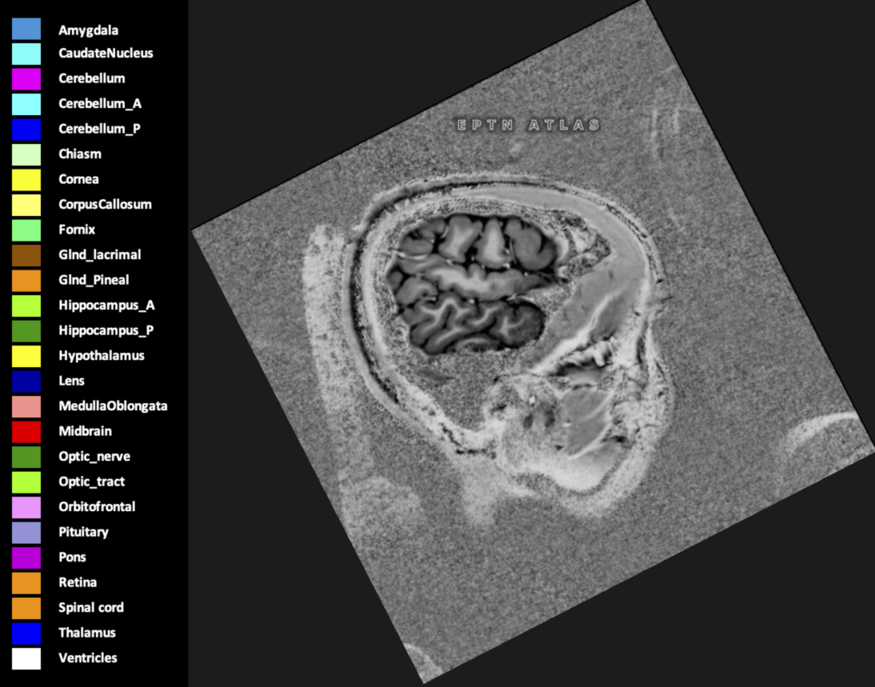

Eekers et al. have published an international neurological atlas for contouring of organs at risk in consensus with the European Particle Therapy Network (EPTN) in 2018 and an update in 2021. The purpose of this consensus atlas is to decrease inter- and intra-observer variability in delineating OARs relevant for neuro-oncology.

Included are all OARs known to be relevant for radiation-induced toxicity in neuro-oncology: brain, brainstem (midbrain, pons, medulla oblongata), chiasm, cerebellum (anterior & posterior), cochlea, cornea, hippocampus (anterior & posterior), hypothalamus, lens, lacrimal gland, optic nerve, pituitary, skin, and vestibular & semicircular canals. To further facilitate research on cognition, vision and radiological changes after irradiation of the brain, potential clinically-relevant OARs are included: amygdala, caudate nucleus, cerebellum (anterior & posterior), corpus callosum, fornix, macula, optic tract, orbitofrontal cortex, periventricular space (PVS), pineal gland, and thalamus.

Three-dimensional delineation of the 25 consensus OARs for neuro-oncology are shown on CT (WW/WL 120/40, 3000/600), 3T MR images, (T1Gd, T2FLAIR 1mm) and 7T MR (MP2RAGE 0.7 mm). All are presented in transversal, sagittal and coronal view.